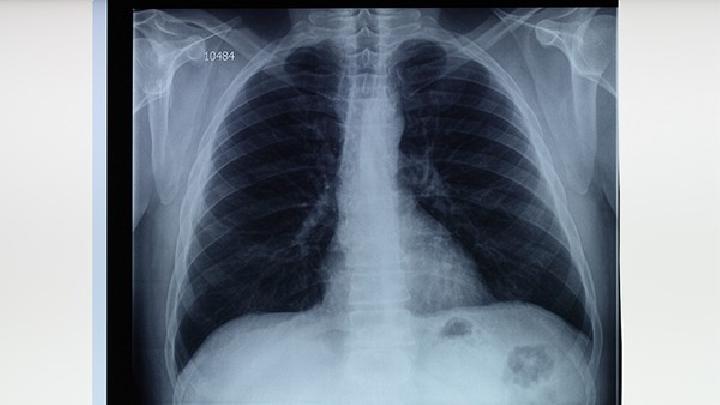

病理变化

1.尘肺结节眼观:病变呈圆形,境界清晰,灰黑色,触感坚实。镜检:或硅结节,即具有胶原纤维核心的粉尘病变;或混合尘结节,即胶原纤维与粉尘混合,但胶原纤维成分占50%上述病变;或硅结核结节,即硅结节或混尘结节与结核病变混合形成的结节。

2.尘肺弥漫性纤维化呼吸细支气管、肺泡、小叶间隔、小支气管、小血管周围、胸膜下部粉尘沉积引起的弥漫性胶原纤维增生。

3.尘斑眼观:病灶呈深黑色,质地柔软,境界不清,直径1 5mm以上扩大的气腔(病灶周肺气肿)。镜检:网织纤维、胶原纤维与病灶粉尘混合,胶原纤维成分不足50%。病变与纤维化肺间质相连呈星芒状,伴有周肺气肿。

4.尘块纤维化眼观:病变为2厘米x2厘米x2厘米以上的灰黑色或黑色纤维块,质地坚韧。镜像检查:或将尘肺结节融合成大量尘胶原纤维化,或由各种尘肺病变的混合组成。

5.粉尘反应是指淋巴结粉尘沉积、巨噬细胞反应、肺引流区轻微纤维组织增生等。